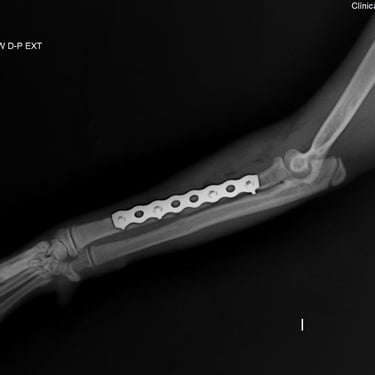

Placas y tornillos: permiten la fijación rígida del foco de fractura, logrando compresión interfragmentaria o neutralización de fuerzas. Son ideales para fracturas diafisarias y metafisarias, ya que brindan excelente estabilidad y control de la alineación ósea.

Placas bloqueadas (LCP): sistema de estabilidad angular donde los tornillos se fijan a la placa, formando un constructo rígido que no depende del contacto íntimo con el hueso. Son especialmente útiles en fracturas conminutas o en pacientes con hueso osteopénico.